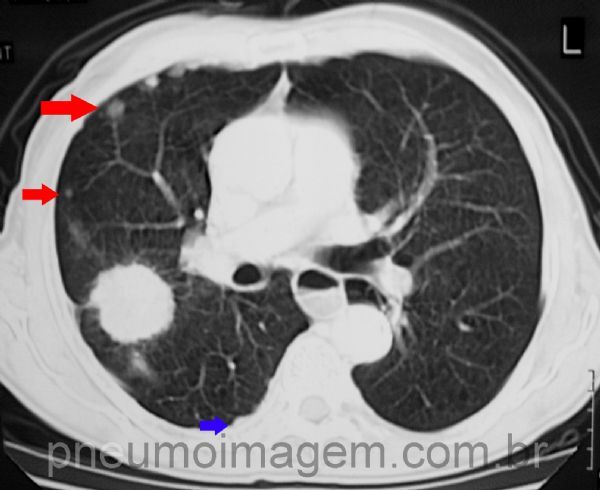

ADENOCARCINOMA COM METÁSTASES PLEURAIS

Adenocarcinoma é um dos quatro principais tipos de neoplasias do pulmão e geralmente se apresenta como um tumor periférico. Neste caso, massa periférica de contornos mal definidos em lobo superior direito. Observe que o seio costofrênico direito está discretamente velado, compatível com derrame pleural.

Corte tomográfico demonstrando que a massa possui contornos espiculados e está em contato com a pleura. Diversos nódulos satélites à lesão configurando doença metástatica (setas vermelhas). Em azul, irregularidade da superfície pleural compatível com implante de metástase.